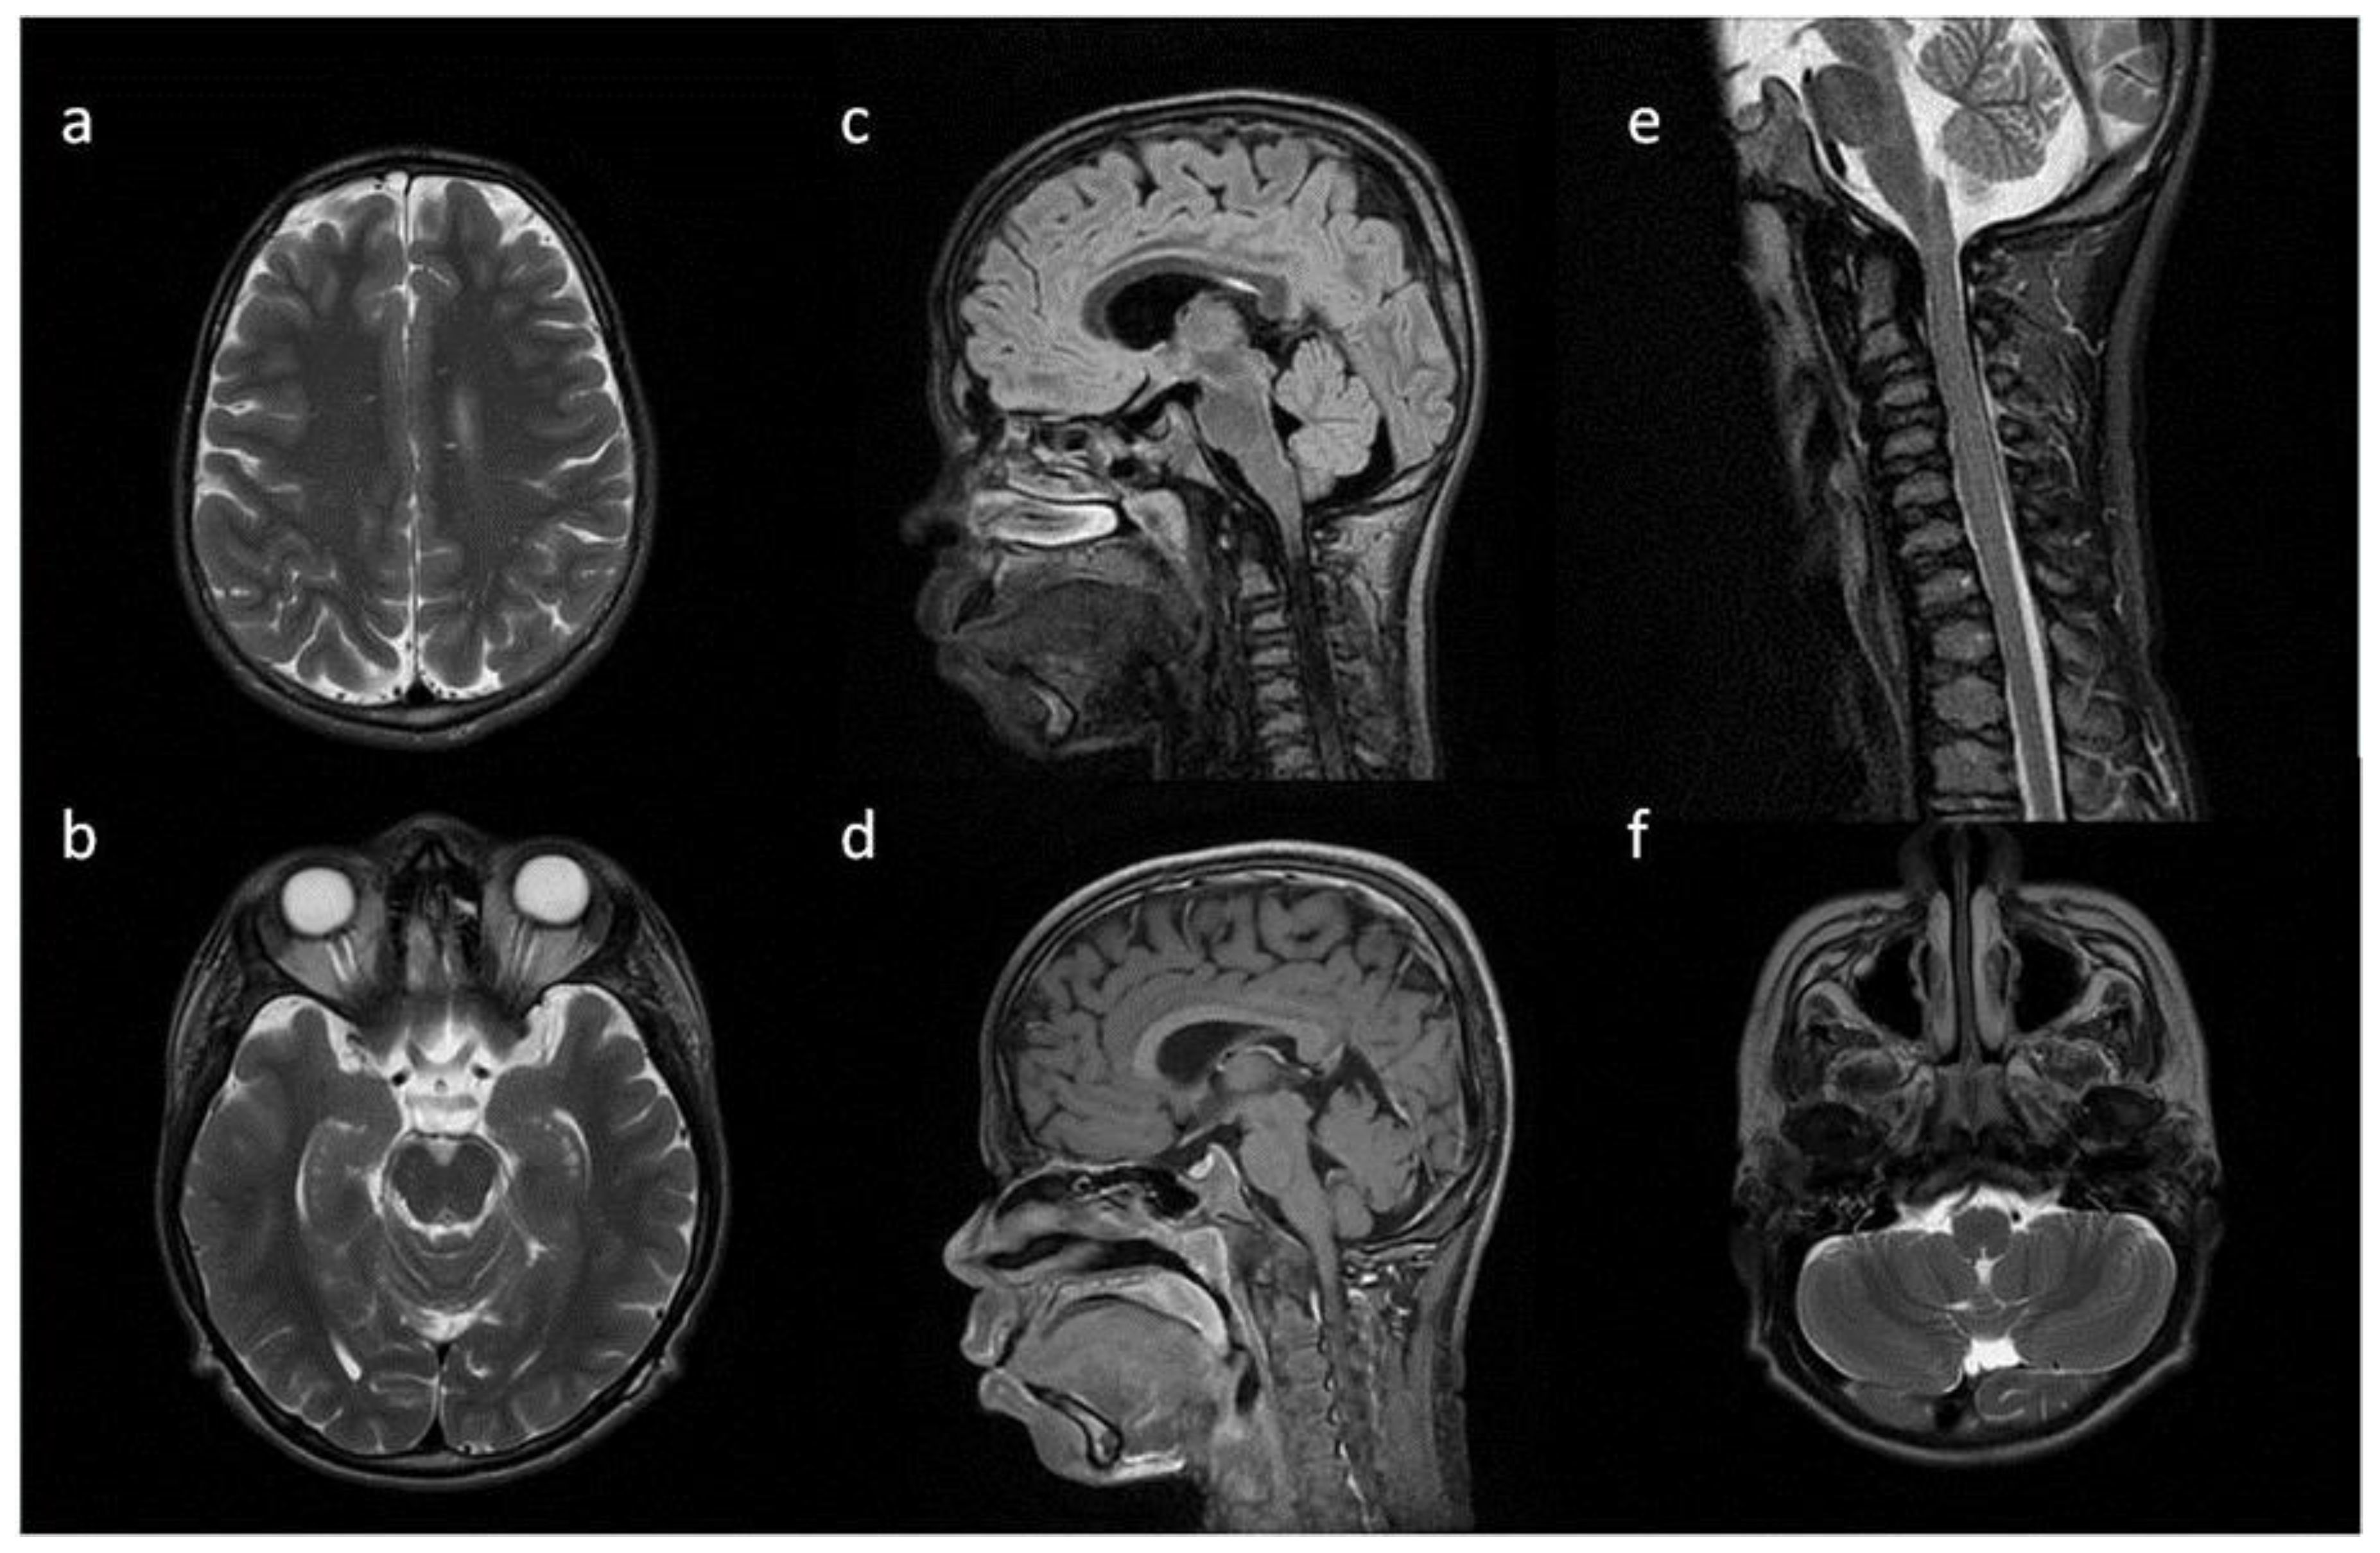

| Patient No | 1 | 2 | 3 | 4 | 5 | |

|---|---|---|---|---|---|---|

| age at exam | 4 mo | 3 yo | 1 y 2 mo | 1 y 11 mo | 3 y 2 mo | 14 yo |

| radiological imaging | ||||||

| WM signal abnormalities | + | + | + | |||

| areas of delayed myelination | + | + | + | + | + | |

| enlarged perivascular spaces | + | + | + | + | ||

| narrow corpus callosum | + | +/− | + | + | ||

| prominent ventricular system | +/− | + | +/− | + | + | |

| arachnoid cyst | + | + | ||||

| optic nerve sheath enlargement | + | + | ||||

| J-shaped sella turcica | + | + | + | +/− | + | +/− |

| craniocervical junction distortion | + | +/− | + | + | ||

| posterior fossa horns | + | + | + | + | ||

| fluid effusion temporal bone | + | + | + | + | +/− | |

| closed sagittal suture | + | + | + | |||

| vertebral bodies deformity | + | + | ||||

| intervertebral disc anomalies | + | + | ||||